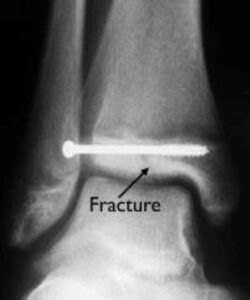

Understanding Ankle Fractures in Children

In children and adolescents, ankle fractures typically affect the tibia or fibula, often involving the growth plates—specialized areas of cartilage near the ends of long bones. Growth plates play a critical role in bone development, gradually hardening into solid bone as the child matures. However, because these growth plates are the last parts of the bones to solidify, they are particularly prone to injury and fractures.

As adolescents approach the end of their growth phase, growth plates begin to close and harden, making them susceptible to transitional fractures during this maturing stage. Two common types of transitional ankle fractures are triplane fractures and Tillaux fractures, which require specific treatment approaches depending on their severity and location (refer to the Treatment section for more details)